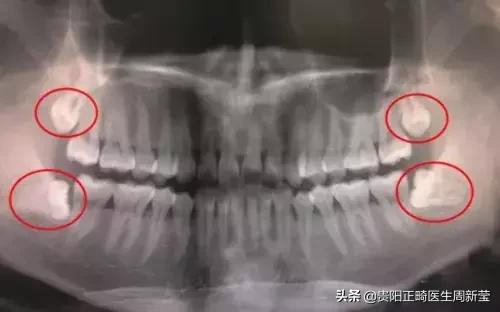

从功能上来讲,第三磨牙属于多余的牙,28颗牙已经可以满足现代人的需求。而且,由于智齿萌出较晚,往往没有足够的位置,智齿很少有能长好的,要么长不出来,要么长得不正。

长不出来,牙龈就会包住智齿,造成牙龈发炎、口腔异味等。

长不正,就是指智齿不能以正常的姿态长出来,它很可能倾斜,把正常的牙齿抵住了造成牙列不齐,甚至导致龋坏。对于长得不好的智齿,可以进行预防性拔除。